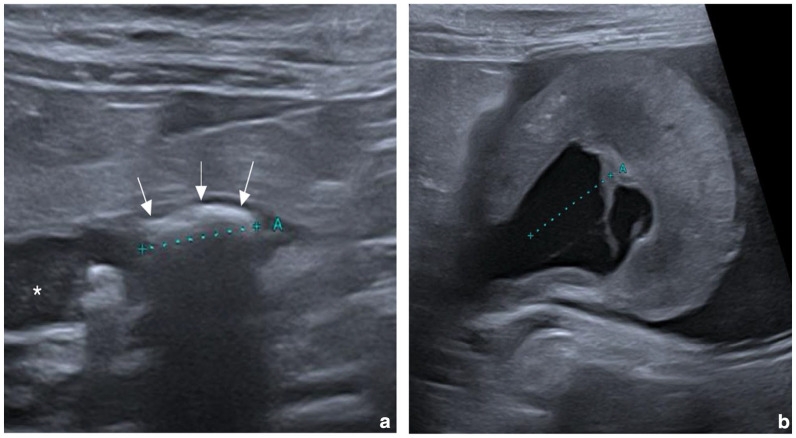

病例总结:一只2岁雌性绝育家短毛猫,有1周嗜睡和吞咽困难的病史,被送到兽医教学医院。体格检查发现严重的左肾肿大,高热和腹痛。腹部超声显示左侧输尿管因输尿管结石阻塞而扩张,并伴有明显的囊下积液。尿液分析显示尿液呈碱性,有鸟粪石结晶。肾盂及膀胱尿液培养假中葡萄球菌阳性。怀疑因存在产脂细菌而感染鸟粪石输尿管结石。通过输尿管切开术取出输尿管结石,并顺行放置临时输尿管支架。红外光谱结果显示为纯鸟粪石尿石症。手术后35天通过膀胱镜取出支架。在6个月的随访中,这只猫仍然表现良好。相关性和新信息:据作者所知,这是猫因肾盂肾炎导致鸟粪石输尿管结石的第一例。

Case summary: A 2-year-old female spayed domestic shorthair cat with a 1-week history of lethargy and dysorexia was presented to a veterinary teaching hospital. Physical examination identified severe left nephromegaly, hyperthermia and abdominal pain. Abdominal ultrasound revealed a left ureteral dilation due to obstruction by a ureterolith, associated with marked subcapsular effusion. Urinalysis showed alkaline urine with crystals of struvite. Culture of urine from the renal pelvis and the urinary bladder was positive for Staphylococcus pseudintermedius. An infected struvite ureterolith due to the presence of urease-producing bacteria was suspected. The ureterolith was removed via ureterotomy and a temporary ureteral stent was positioned in an antegrade fashion. Results of infrared spectroscopy showed pure struvite urolithiasis. The stent was removed via cystoscopy 35 days after surgery. The cat was still doing well at the 6-month follow-up.